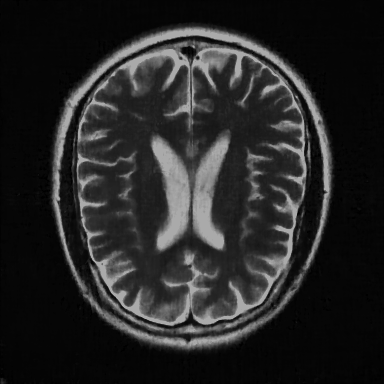

This article presents a novel undersampled magnetic resonance imaging (MRI) technique that leverages the concept of Neural Radiance Field (NeRF). With radial undersampling, the corresponding imaging problem can be reformulated into an image modeling task from sparse-view rendered data; therefore, a high dimensional MR image is obtainable from undersampled $k$-space data by taking advantage of implicit neural representation. A multi-layer perceptron, which is designed to output an image intensity from a spatial coordinate, learns the MR physics-driven rendering relation between given measurement data and desired image. Effective undersampling strategies for high-quality neural representation are investigated. The proposed method serves two benefits: (i) The learning is based fully on single undersampled $k$-space data, not a bunch of measured data and target image sets. It can be used potentially for diagnostic MR imaging, such as fetal MRI, where data acquisition is relatively rare or limited against diversity of clinical images while undersampled reconstruction is highly demanded. (ii) A reconstructed MR image is a scan-specific representation highly adaptive to the given $k$-space measurement. Numerous experiments validate the feasibility and capability of the proposed approach.